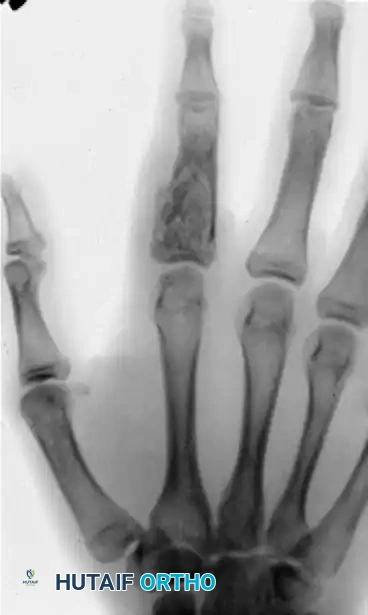

Expanding intraosseous tumor of the fifth metacarpal exhibiting a ground-glass appearance. Note the intact cortical shell causing pressure deformity on the adjacent fourth metacarpal.

* Radiographic Appearance: Osteoblastomas are highly expansile. They produce gross metacarpal or phalangeal deformities. Radiographically, they exhibit a characteristic "ground-glass" appearance due to the varying degrees of matrix ossification. Despite tremendous expansion, the cortical shell typically remains intact, though it may become paper-thin and cause pressure deformities on adjacent bones.